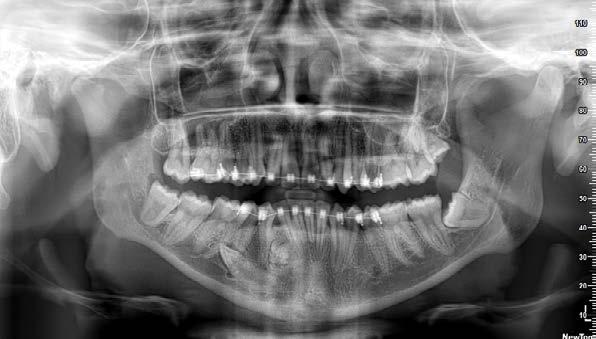

Figura 3. Radiografía panorámica del paciente donde observamos la pérdida ósea ocasionada por la periodontitis agresiva y los dientes que se encuentran con el único sostén de los tejidos gingivales como los del frente anterior. Además, vemos cómo los molares de ambos cuadrantes superiores deben ser extraídos por presentar un mal pronóstico desde el punto de vista periodontal y restaurador.

Presentamos el caso de un paciente de 35 años, fumador, con enfermedad periodontal agresiva en fase avanzada y un deficiente control de la higiene oral. El paciente acude a nuestro centro solicitando un tratamiento restaurador con implantes dentales, tras haber experimentado varios fracasos con prótesis removibles previas. Durante la exploración intraoral, se observa periodontitis avanzada, con una significativa pérdida de inserción en la mayoría de los dientes, un control inadecuado de la placa bacteriana, y una prótesis removible mal ajustada anclada a dientes con movilidad (Figura 1 y 2). En la radiografía panorámica inicial podemos constatar la gran pérdida ósea horizontal, en todas las piezas dentales, con algunas de ellas ancladas únicamente en el tejido gingival. Además vemos también en la imagen

cómo existen varias piezas dentales con pronóstico dudoso con grandes caries con afectación radicular que deben ser extraídas, como los molares de los sectores posteriores maxilares, tanto derecho como izquierdo (Figura 3).